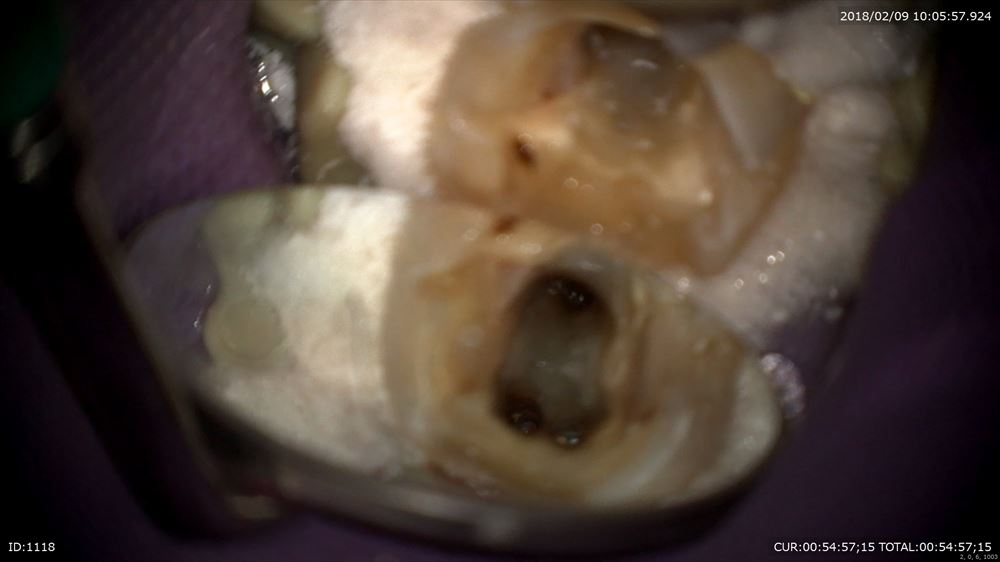

本日もラバーダム

丁寧に観察

綺麗になり根管充填

MTAをシーラーに。

OK

このケースは虫歯